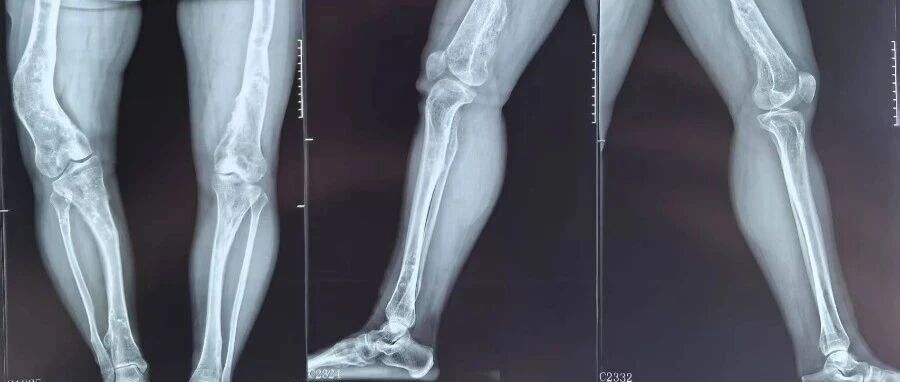

日常走路崴脚你是不是也觉得 “小事一桩,歇两天就好”?千万别再抱有这种想法!68 岁的王大爷就因轻视一次普通崴脚,险些漏诊多处骨折,万幸及时完善检查、规范治疗,才避免了创伤性关节炎、踝关节不稳等终身行走隐患。崴脚从不是简单的 “小磕碰”,轻视的代价可能远超想象!68 岁的王大爷散步时不慎崴伤脚踝,当时踝关节虽肿胀疼痛,但还能勉强行走,他便没放在心上,只当是普通磕碰。在北京积水潭医院郑州医......